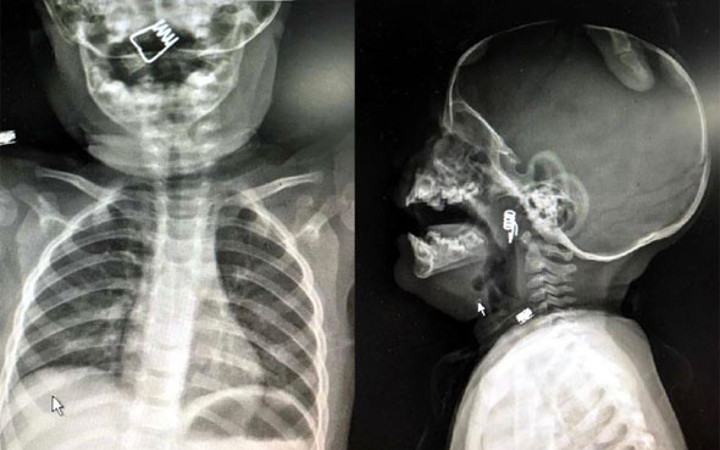

NEVŞEHİR'de inanılması güç bir olay yaşandı. 1 yaşındaki erkek bebek Ö.Y. önüne konulan çamaşır mandalıyla oynarken mandal dağıldı. Minik bebek de mandalın metal yayını hemen ağzına attı. Bebeğin ani tepki verip yutkunması sonrası metal yay, çocuğun boğazına kaçtı. Hastanede çekilen röntgende yayın yeri tespit edildi. Bebeğin nefes borusuna saplanan yay başarılı bir operasyonla çıkarıldı.

Nevşehir Devlet Hastanesi Acil Polikliniği'ne getirilen bebeği, Acil Nöbetçi doktoru Mustafa Alpaslan muayene ederek gerekli tetkikleri yaptı. Çekilen röntgen filmlerinde mandal yayının lokalizasyonu ve durumu belirlendi. Daha sonra, KBB Uzmanı Op. Dr. Ahmet Cevatzade tarafından yapılan başarılı ameliyat sonucunda bebeğin genzine saplanan mandal yayı çıkartıldı.